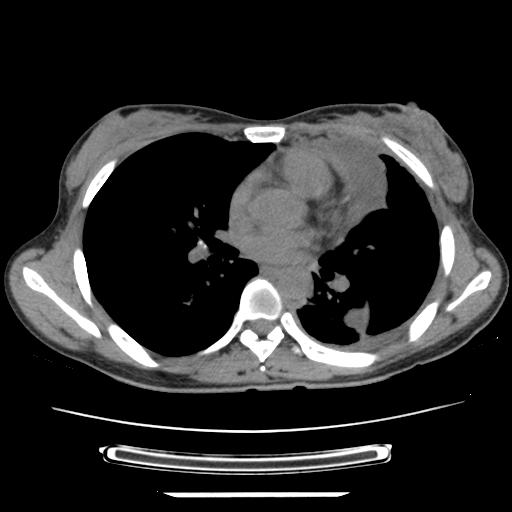

女,29岁,胸部不适,在外院胸片提示胸腔积液,到我院ct检查。

纵膈窗

左侧纵隔胸膜包裹性积液、左侧胸腔积液、胸膜肥厚粘莲,考虑结核性胸膜炎

左肺上叶不张,左侧胸水,叶间裂积液,纵隔淋巴结,脾脏钙化,考虑左肺上叶支气管内膜结核,结核性胸膜炎,脾结核

考虑两肺结核,左侧包裹性积液,叶间积液。

支持两肺继发性肺结核,左侧胸膜腔包裹性积液、胸膜肥厚,脾内多发钙化(结核钙化)。